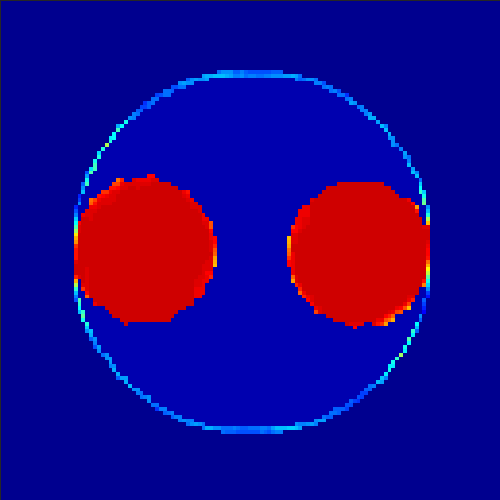

5.2 Monte Carlo Simulation

In order to test the behaviour of the proposed method in a more realistic, random-based test case, we performed a Monte Carlo simulation for dynamic SPECT imaging. First, we created a simple image phantom consisting of an outer and two inner circles which represents the structure of the region of interest (see figure 8(a)). Within those regions we assumed concentration curves over a time period of 90 time steps as displayed in figure 8(b). Based on the tracer intensity in an image frame at each time step, we created a variable number of random decay events (where the number is proportional to the average concentration in one pixel in the whole image frame per time step) with a probability proportional to the concentration in every subregion. They are detected by a virtual double head gamma camera rotating around the patient by 46 degrees per time step, which consists of 374 detector bins. Every simulated decay event is projected onto the scanner and counted by the corresponding detector bin.

In two different tests we fixed the number of events counted by the detector equal to (resp. ) times the average concentration in one pixel. The resulting sinogram images of the accumulated counts in each bin are shown in figure 9.

Based on the sinogram data we applied the proposed algorithm in order to reconstruct the original image sequence. The results for both test cases are shown in figure 10.

As one can see, the method is able to reconstruct the regions properly, even in case of a low count number. Within a number of iterations (average of 100 outer and 10000 inner iterations), the algorithm presents a reasonable reconstruction of the region of interest and the corresponding regional tracer concentration curves. Here, the parameters were not optimized as in the case of the synthesized data sets in the previous section, but kept fixed as , and . With futher optimized parameter values one could possibly provide even better results.